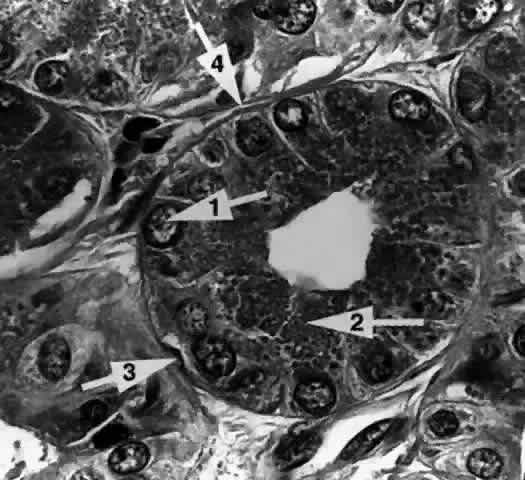

Each lobule consists of a complicated grape-like (Fig. 14) arrangement of acini. Each acinar unit (Fig. 15) consists of a central lumen, a continuous inner layer of columnar secretory epithelial cells, and a surrounding interrupted outer layer of irregularly shaped myoepithelial (basket) cells.9

Fig. 15. The acinar unit. The columnar secretory cell has a basally located nucleus (arrow 1). Zymogenic secretory granules (arrow 2) are seen in the midportion and apical cytoplasm. A myoepithelial cell (arrow 3) is interspersed between the secretory cell and the basement membrane (arrow 4). (H & E, original magnification × 250; Courtesy of Ralph Eagle, MD, Philadelphia, PA)

The acinar secretory cell typically has a basally located nucleus with one or two nucleoli, as seen with electron microscopy. The predominant structures in its cytoplasm are the numerous zymogenic secretory granules located mainly in the apical or midportions of the cell9 (see Fig. 15).

Myoepithelial cells (see Fig. 15) appear as flattened, stellate, or spindle-shaped cells interspersed in the basal part of the acinar wall, between the secretory cells and the basement membrane. They are characterized by the presence of cytoplasmic myofilaments. The myofilaments consist of actin-type filaments in a parallel fashion, in some areas resembling fusiform smooth muscle.9,11

A thick, often multilayered basement membrane (see Fig. 15) surrounds the outer surface of the acinus, separating it from the intralobular connective tissue. Collagen fibrils, capillaries, unmyelinated nerve fibers, fibroblasts, plasma cells, and lymphocytes can be found within this connective tissue. The plasma cells have been shown to produce IgA, an immunoglobulin typically elaborated at mucosal surfaces. Acetylcholinesterase activity has been found around the acini, particularly adjacent to the myoepithelial cells, suggesting that they are the primary neural target for parasympathetic activity.16,17